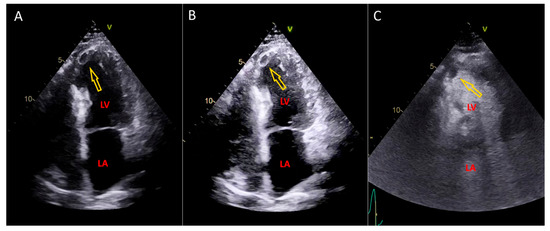

Postprocessing Method for Enhanced Left Ventricular Thrombus Detection in Echocardiography

Background and Objectives: The incidence of left ventricular thrombus has decreased in recent years due to advancements in reperfusion strategies for acute myocardial infarction and the use of medications to reduce ventricular remodeling. However, the accurate detection of thrombus remains crucial. Echocardiography is [...] Read more.

Background and Objectives: The incidence of left ventricular thrombus has decreased in recent years due to advancements in reperfusion strategies for acute myocardial infarction and the use of medications to reduce ventricular remodeling. However, the accurate detection of thrombus remains crucial. Echocardiography is a primary diagnostic tool for thrombus detection, but in cases where the apex of the left ventricle is not clearly visualized, contrast injection is often required for diagnosis. We developed a postprocessing Left Ventricular Thrombus Detection Method (LVTDM) to enhance image details in the region of interest, enabling diagnosis without additional contrast injection. A purpose of our study is the evaluation of Left Ventricular Thrombus Detection Method. Materials and Methods: We analyzed echocardiography video files from 29 patients with apical wall motion abnormalities using LVTDM to identify the presence or absence of thrombus in the left ventricular apex. The results were verified with diagnoses obtained from the same echocardiography examinations following contrast injection. Our method demonstrated a sensitivity of 100% and a specificity of 83%, with a negative predictive value of 100% for ruling out thrombus. There was a strong correlation in thrombus detection/ruling out between LVTDM and contrast echocardiography. The Left Ventricular Thrombus Detection Method can be integrated into routine echocardiography examinations to effectively rule out thrombus when the apex is not clearly visualized. The implementation of this method has the potential to reduce the need for contrast injection by approximately half for detecting left ventricular thrombus. Full article